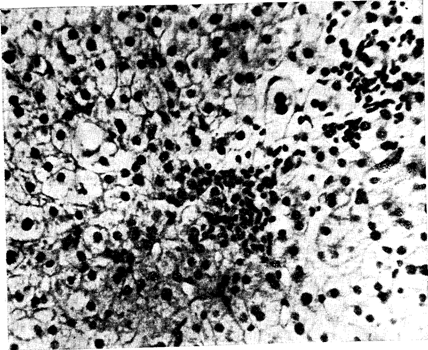

В пунктатах печени больных хроническим персистирующим гепатитом (ХПГ), который развивается у 3—6% больных, перенесших ОВГ-В, и у 10—12% после ОВГ - ни А ни В, наиболее типичной находкой является портальный гепатит — выраженная инфильтрация лимфоидными клетками портальных и пери-портальных областей, не нарушающая целостности пограничной гепатоцитарной пластинки (слой печеночных клеток, отделяющий портальное соединительнотканное пространство от печеночной дольковой паренхимы) или вызывающая лишь незначительную очаговую ее эрозию. Некоторые мерфологи рекомендуют любое нарушение целостности пограничной пластинки рассматривать как проявление ХАГ. По-видимому, решающее диагностическое значение в таких «пограничных» случаях должна иметь динамика заболевания на протяжении нескольких лет. ХПГ протекает без выраженного внутридолько вого фиброза, с полным сохранением структуры печеночных долек, отсутствием мелкоочаговых («ступенчатых») некрозов паренхимы печени (хотя возможны некрозы единичных печеночных клеток), но нередко с мезенхимально-й внутридолько вой реакцией—узелковой гипертрофией и гиперплазией звездчатых ретикулоэндотелиоцитов и с внутридольковыми круглоклеточными инфильтратами [, 1975; Bi anchi L., 1969; Rossler R. et al., 1970]. Возможно развитие портального фиброза и коротких фиброзных септ, проникающих. на небольшое расстояние в паренхиму из расширенных портальных трастов. Своеобразным морфологическим вариантом ХПГ является хронический лобулярный гепатит (центральный гепатит), при котором изменения в пунктате печени напоминают картину реконвалесцентной фазы ОВГ (рис. 5). При этом нерезко выраженные воспалительные круглоклеточные инфильтраты локализуются преимущественно в центральных и промежуточных отделах печеночной дольки. При лапароскопии у больных ХПГ находят умеренно увеличенную красноватого оттенка печень с гладкой поверхностью, местами с очаговыми поверхностными утолщениями серозной оболочки [Логинов А. С., 1969].

Рис. 5. Лобулярный гепатит. Видны внутридольковые лимфоидно-клеточные инфильтраты. Микрофото. 16Х7. Окраска гематоксилин-эозином.